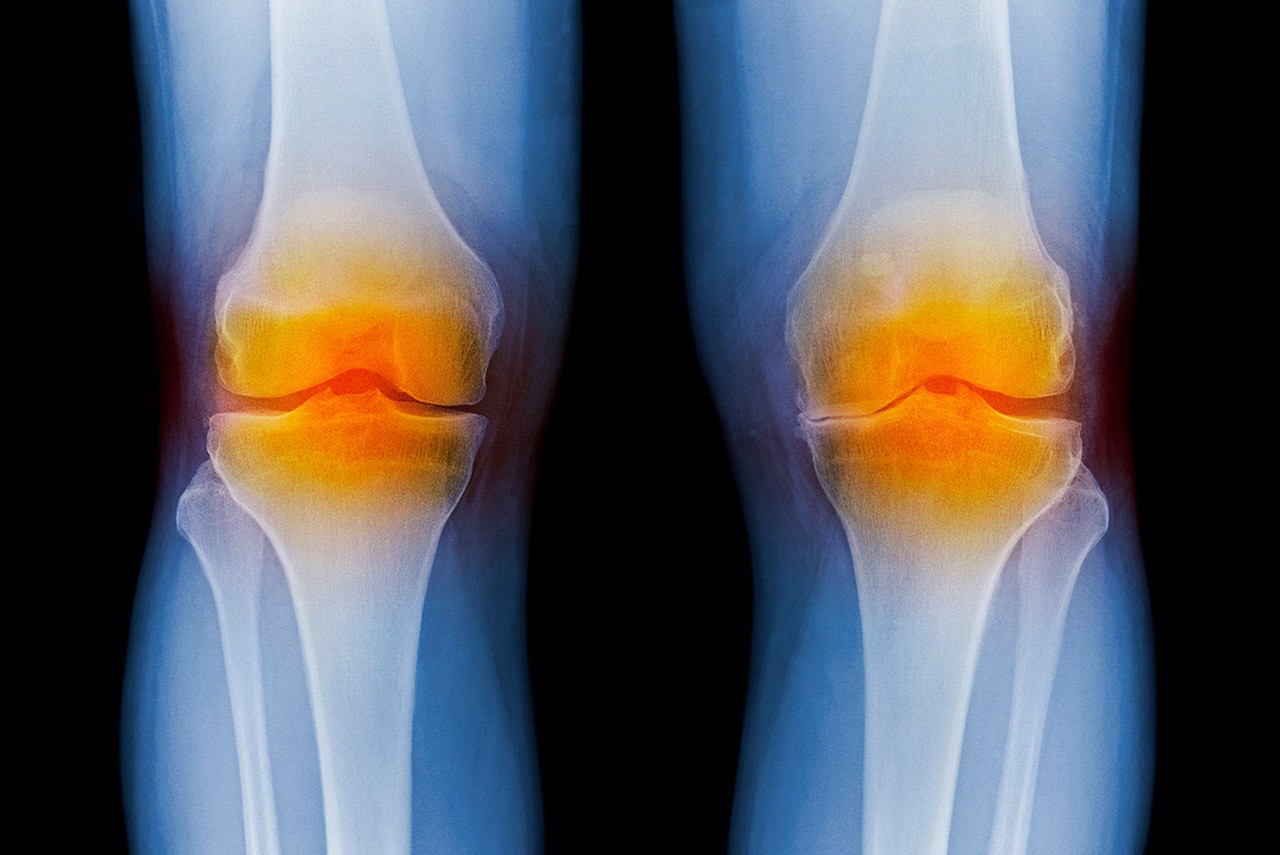

knee X-ray

A Joint Effort

Engineering dean partners with fellow researchers to develop breakthrough therapy for osteoarthritis

By Queen Muse